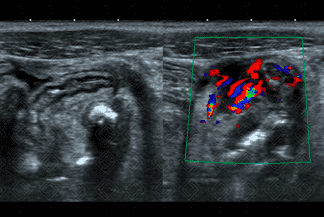

Texto alternativo para a imagem Figura 3. Créditos: Athena Hub/Medical Harbour

Descrição da figura 3: Tomografia computadorizada do abdome com contraste oral : Plano coronal evidenciando apêndice cecal de calibre aumentado, medindo 1,9 cm (seta vermelha). Observa-se, ainda, tênue densificação dos planos adiposos de permeio.